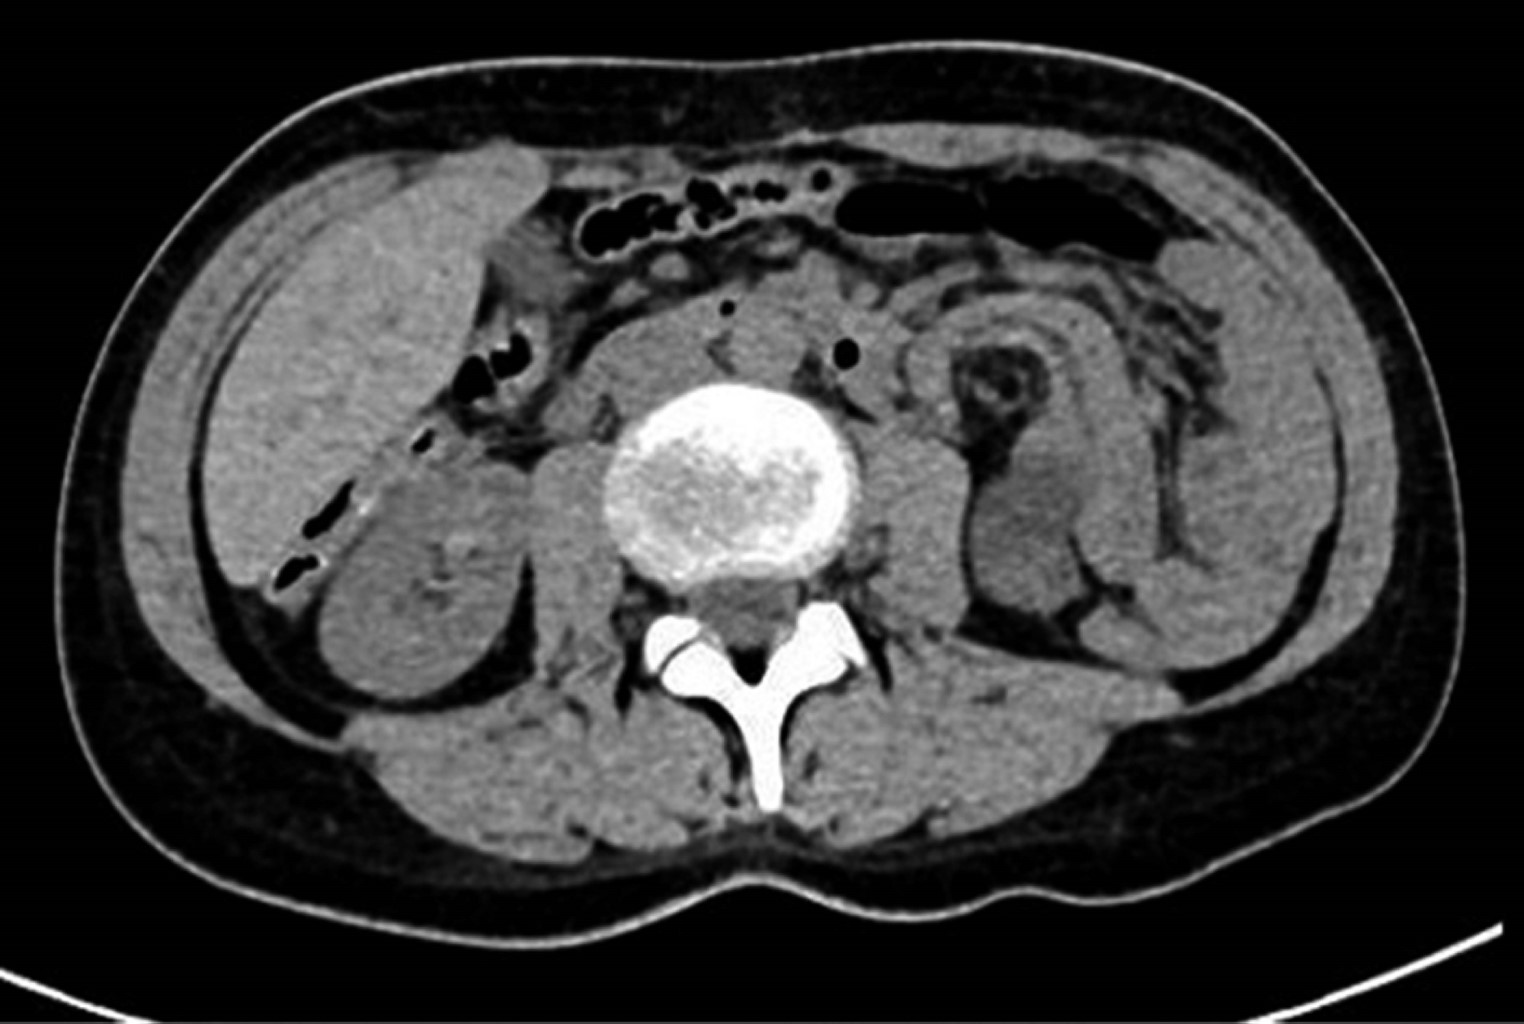

Broad ligament hernias are a rare cause of internal hernia. They can be congenital or acquired, secondary to rupture of a Müller cyst, previous surgeries, pregnancy, birth-related trauma, or pelvic inflammatory disease. We present a 38-year-old female with colicky abdominal pain of four hours of evolution, predominantly in the left flank; the tomography showed hydro-aerial levels in jejunal loops and swirling of the mesentery in the left flank. A laparoscopy was performed, finding an internal hernia with a defect in the left broad ligament, with the content of jejunal loops; the defect was reduced and repaired without complications. Of the intestinal occlusions, 1% are due to internal hernia, and only 4% are of the broad ligament. Tomography is the study of choice, finding a transition zone in the pelvis, dilatation of bowel loops lateral to the uterus, or increased distance between the uterus and one of the ovaries. Laparoscopy is ideal for confirming the diagnosis and for management. These hernias are a rare type of internal hernias and should be suspected, especially in cases with a history of surgery, obstetric trauma, or pelvic inflammatory disease.

Figure 1

Figure 2

Figure 3